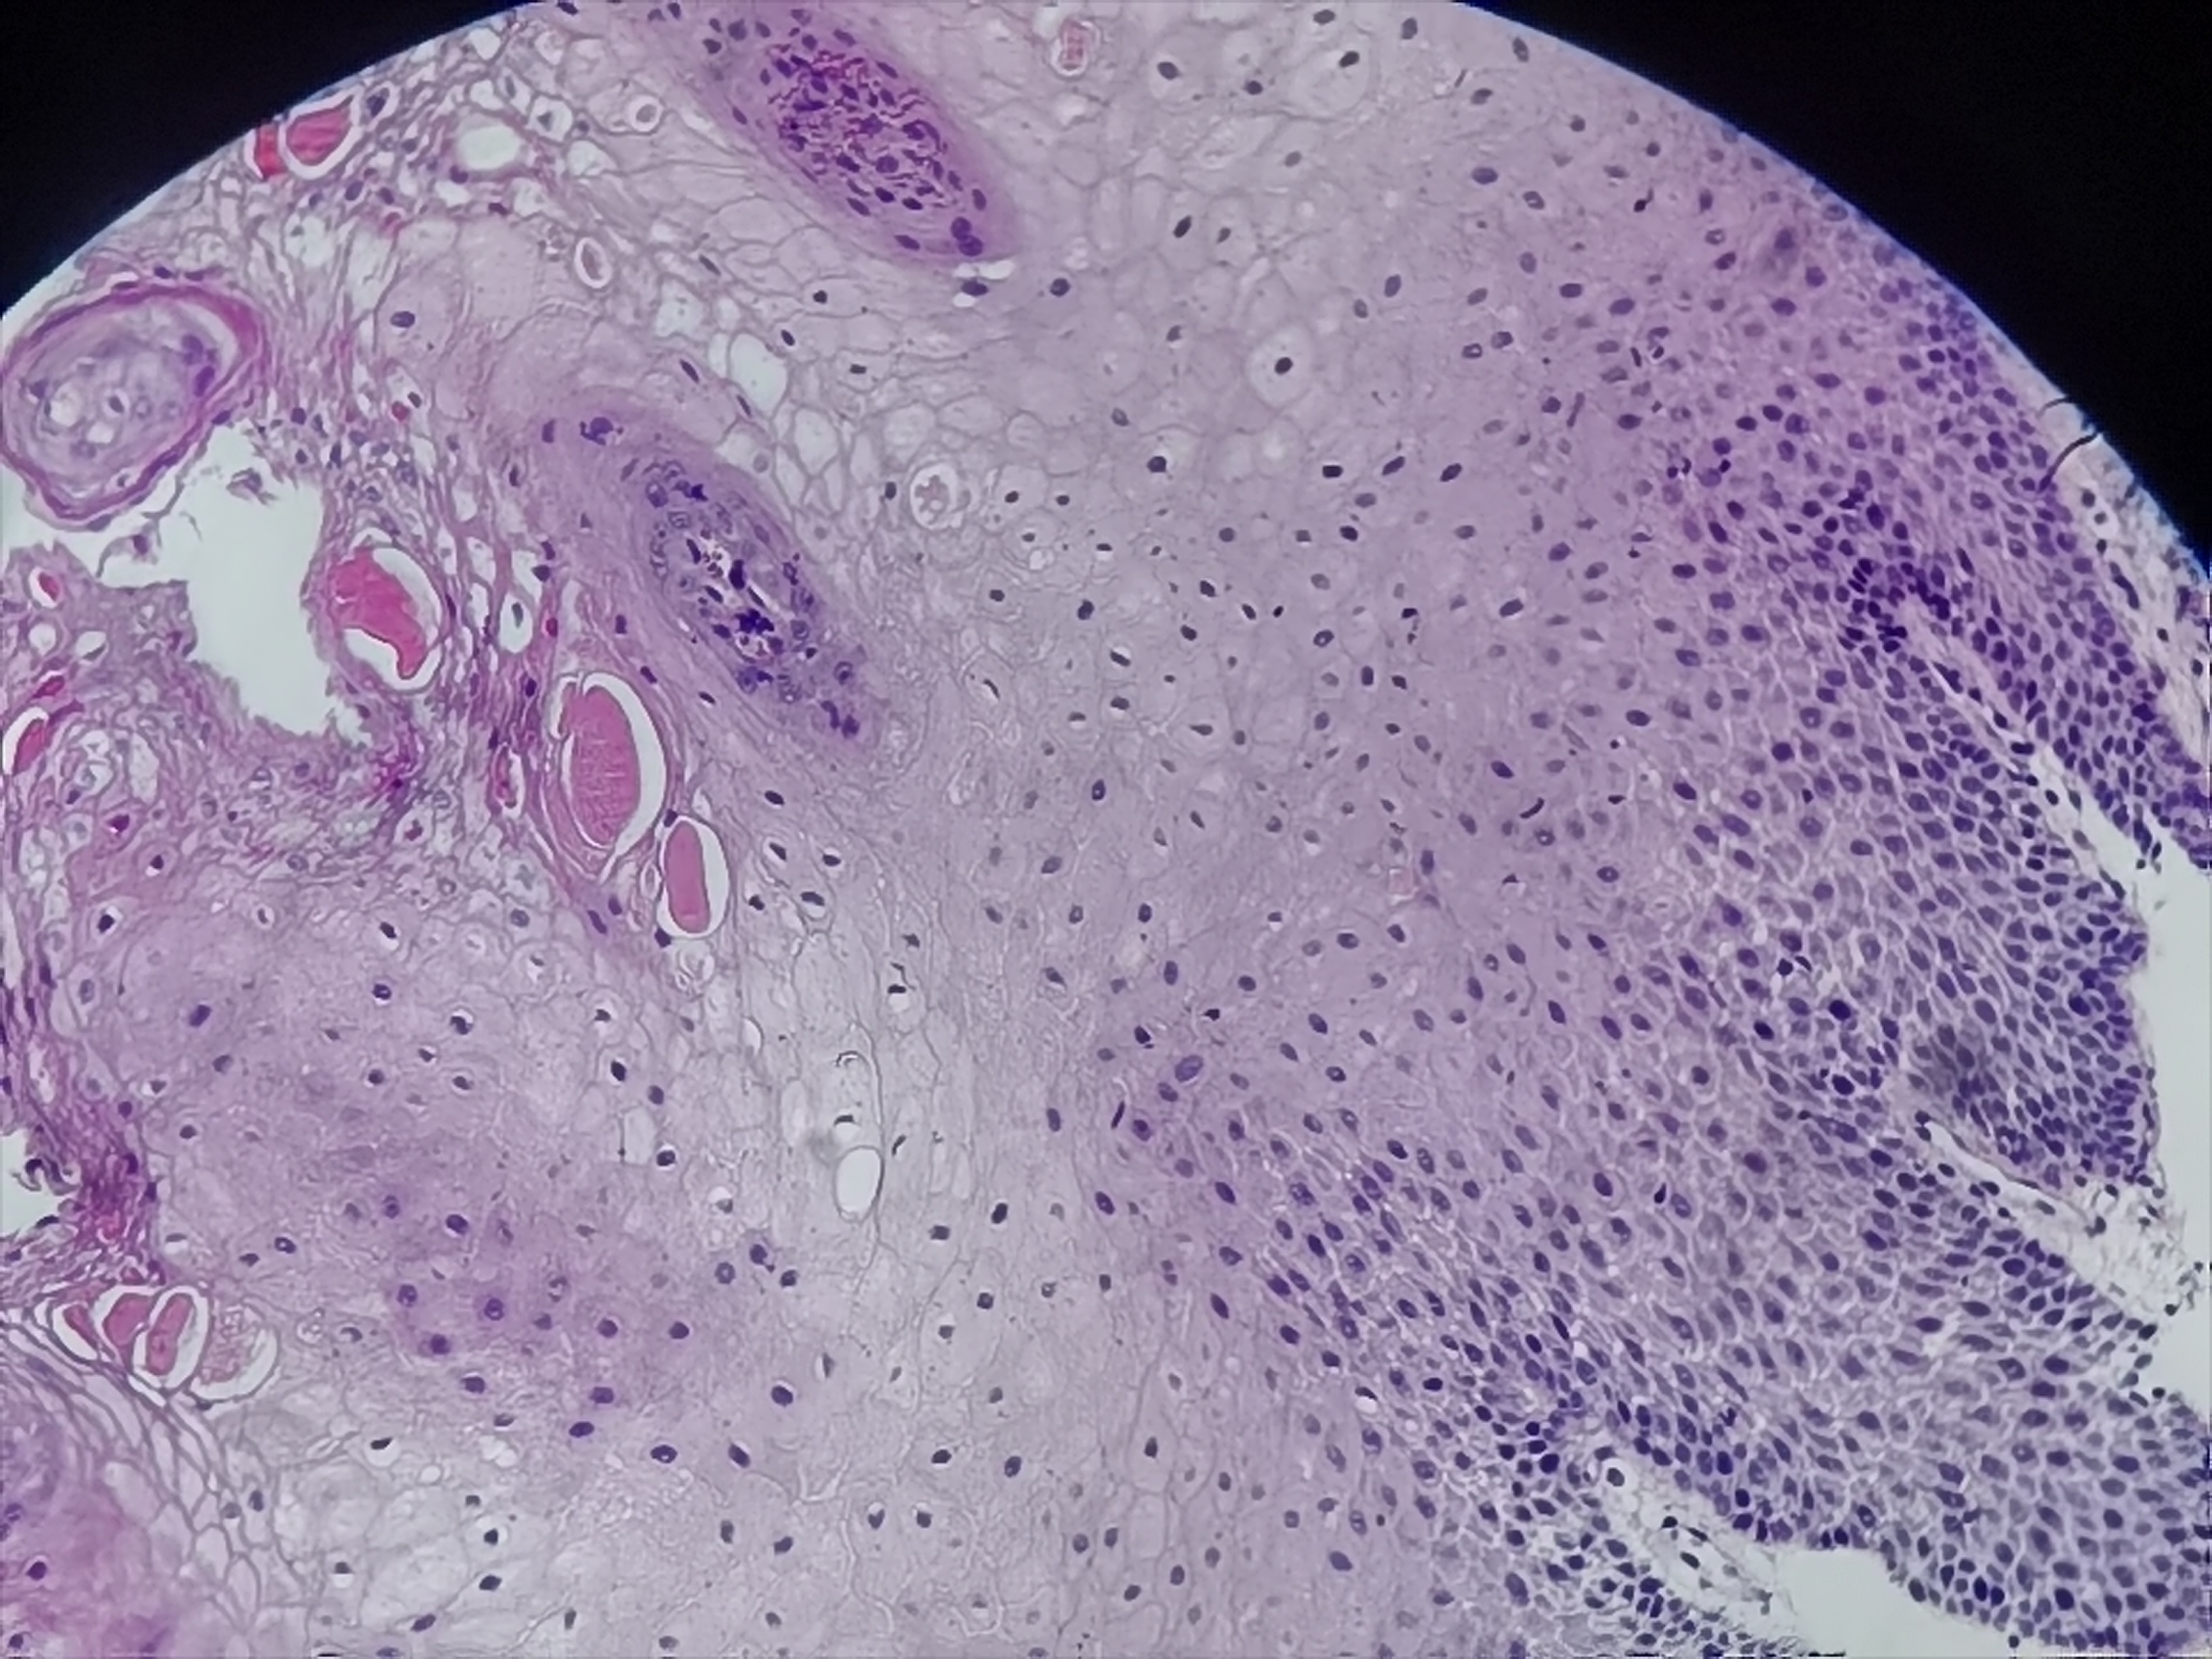

食管活检

食管:距门齿35cm至贲门口可见菜花样改变,有溃疡,触碰有出血

食管粘膜活检

灰白灰红组织3块

鳞皮乳头状增生伴粘膜慢性活动性炎,图11-14需要排除一下